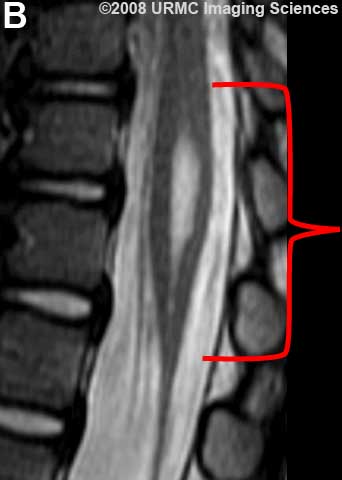

Желудочек терминальный (ventriculus terminalis, PNA, BNA, JNA; син. Краузе желудочек) — расширение в концевом отрезке центрального канала спинного мозга, расположенное в мозговом конусе вблизи от задней его стенки.

Желудочек терминальный

МРТ.  Терминальный желудочек

http://www.radsource.us/clinic/0807